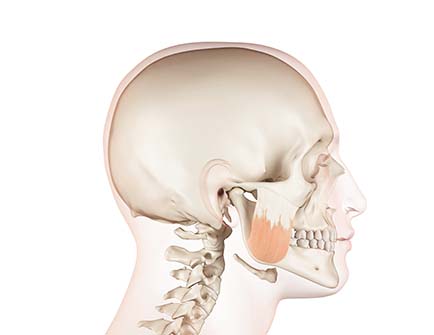

리페이스는 재수술 시 안면 윤곽 개선

구강 기능 회복을 통합적으로 설계합니다.

교정요소 재수술 접근법

• 뼈 비대칭

절단된 뼈 재배치와 함께

자연스러운 윤곽을 생성

• 교합 불안정

부정교합 원인 제거 및

치아 기능 정상화

• 돌출·후퇴 개선

돌출되거나 후퇴한 하악부를

정상적인 위치로 복구